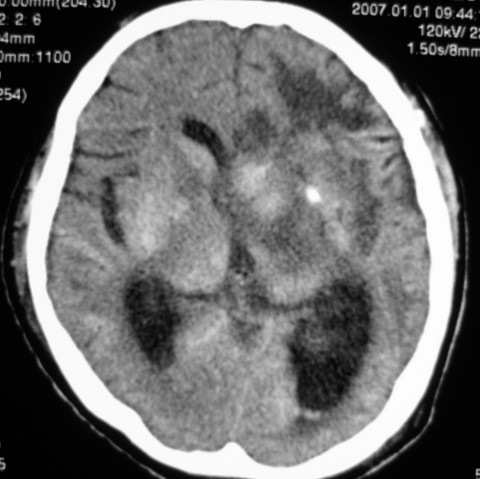

第一次ct片脑出血术后,出血吸收期。第二次ct 片左颞顶枕部及右颞顶部有脑回样高密度影。考虑珠网膜下腔出血。脑出血术后改变,脑出血恢复期 并脑积水。

第一次ct片脑出血术后,出血吸收期。第二次ct 片左颞顶枕部及右颞顶部有脑回样高密度影。考虑珠网膜下腔出血。脑出血术后改变,脑出血恢复期 并脑积水

是蛛网膜下腔出血么?蛛网膜下腔出血应该在脑沟里,而此高密度影是沿脑回分布,应该是脑膜感染后钙化灶形成。

应该是脑回钙化,不是出血

脑回状高密度影,首先要考虑脑颜面血管瘤病,不知高密度区ct值多少,对于鉴别是蛛网膜下腔出血还是钙化有意义,只是病人半月前“钙化”还较局限,因此还是考虑与脑出血有关。当然要密切结合病史及临床,增强扫描有意义。

考虑是脑回钙化,不是出血,什末样的蛛网膜下腔出血是这样的?我没见过!考虑脑炎性钙化,要结合病史!